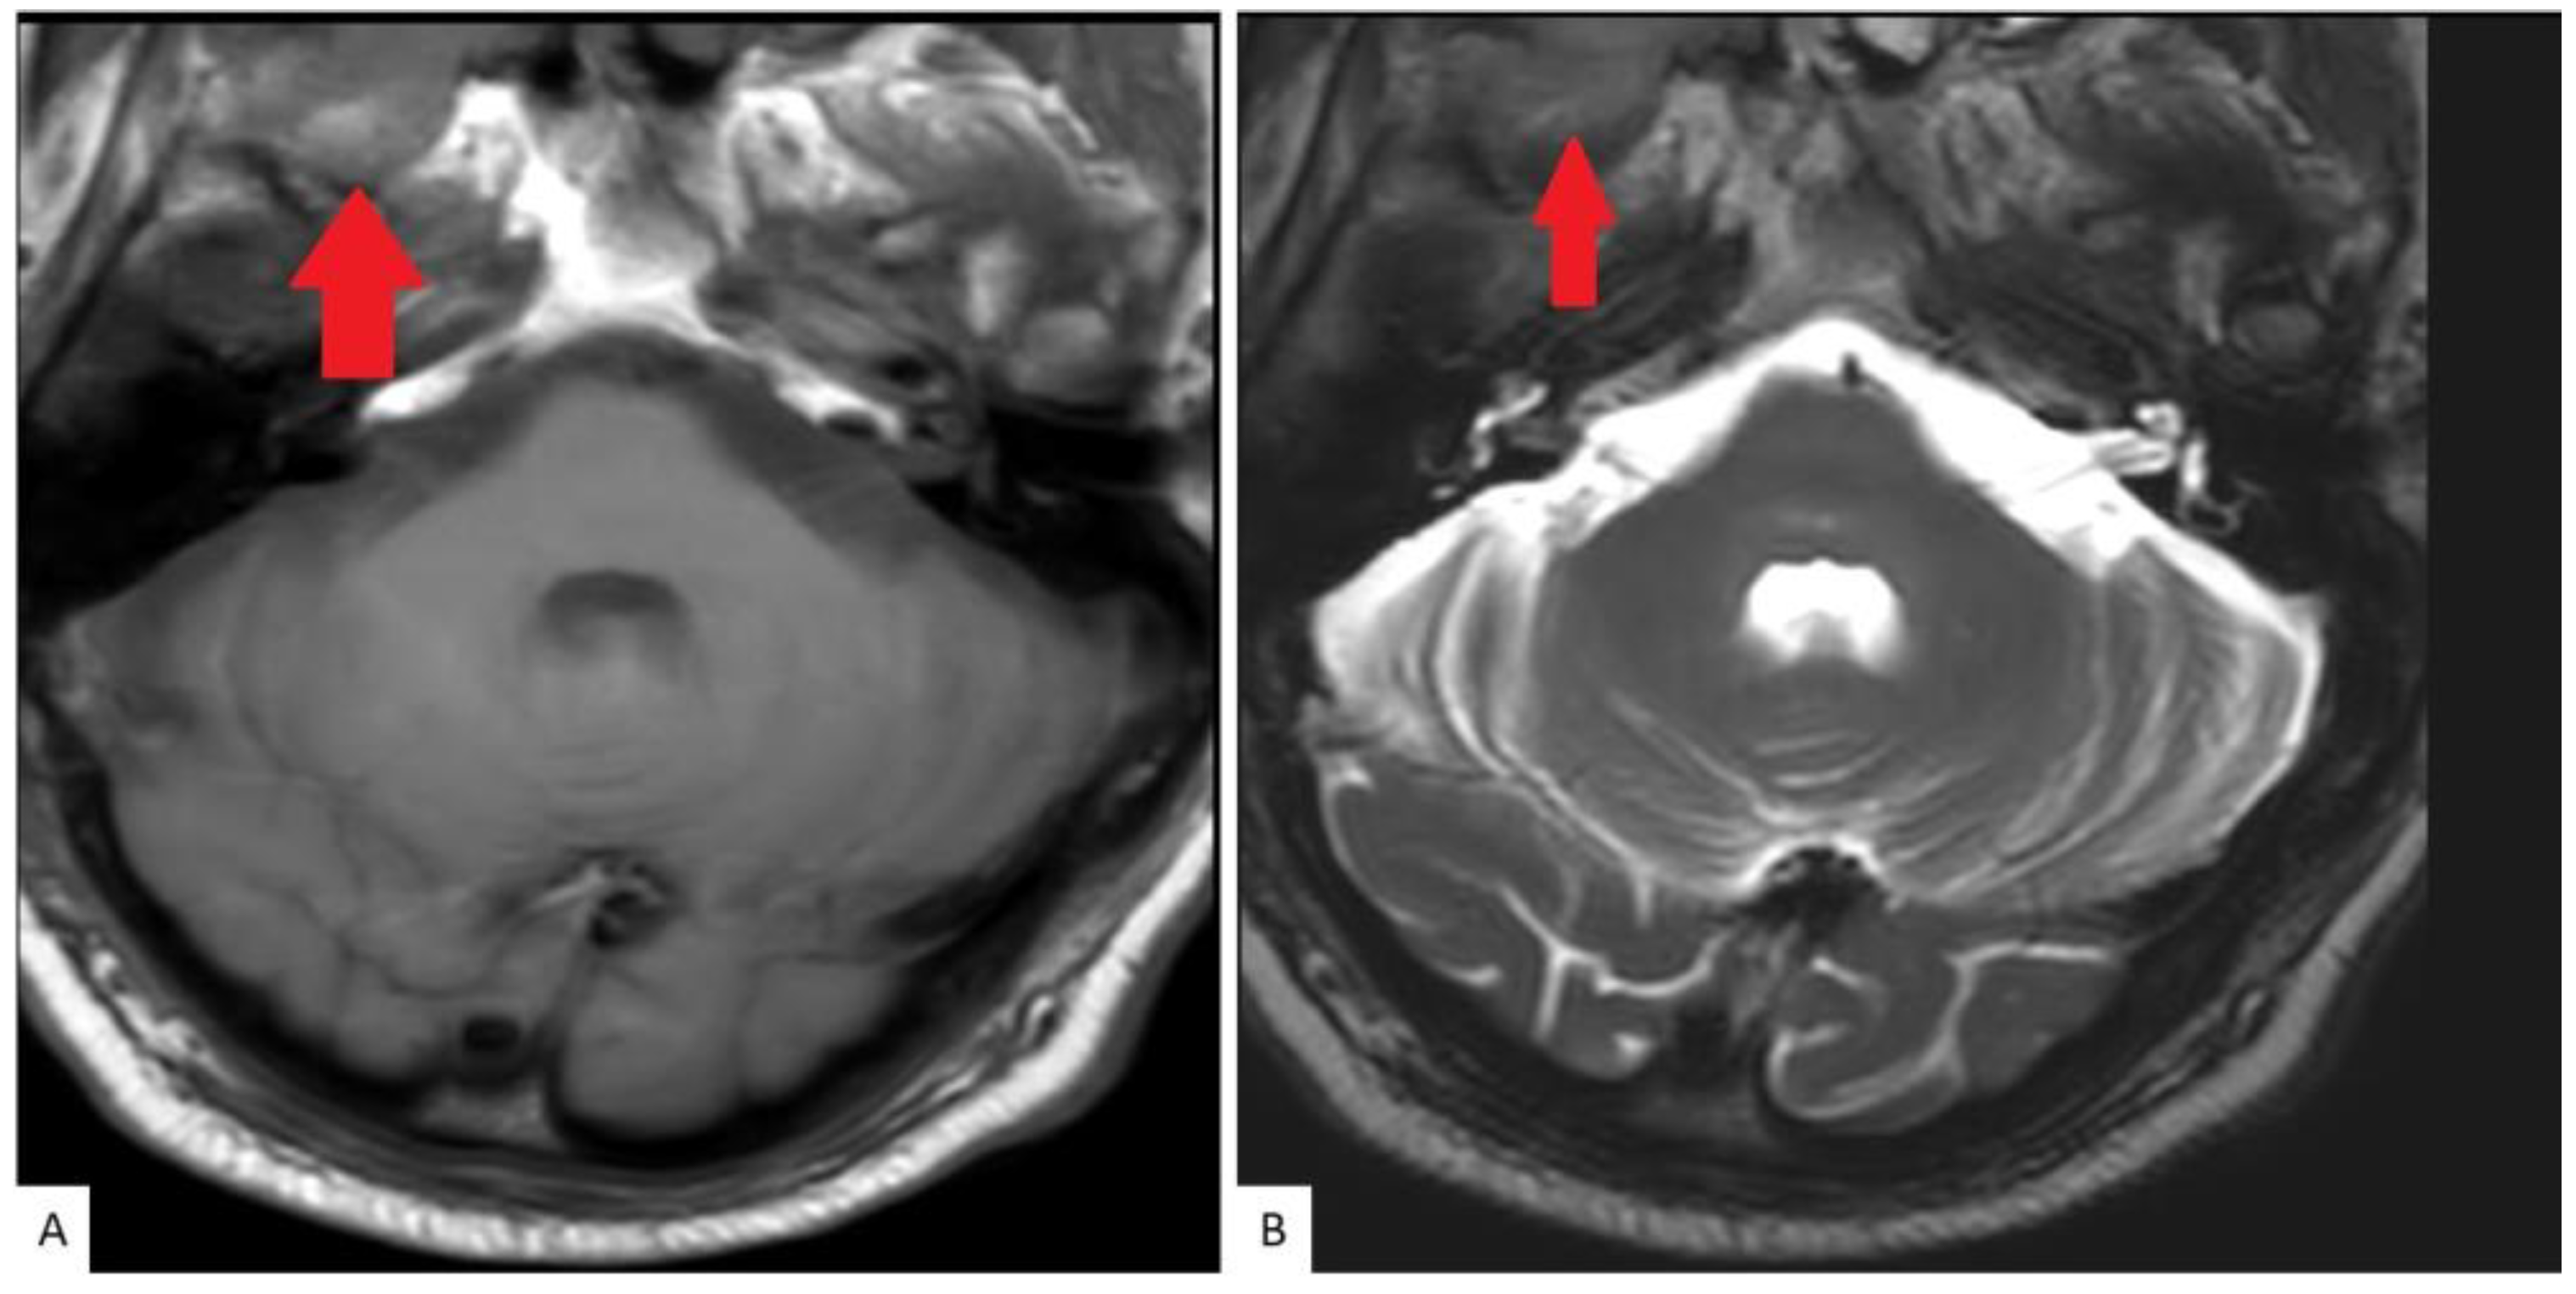

2. Case Presentation